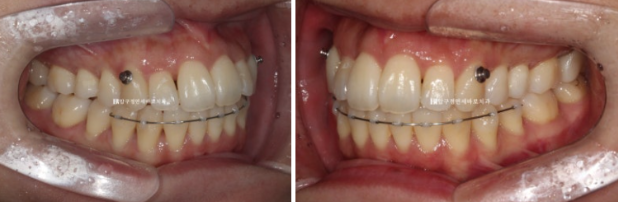

측절치 덧니가 아랫니와 거꾸로 물리는 반대교합을 보입니다.

반대쪽 파란 화살표 부분 작은 어금니 역시 배열에서 튀어나가 있어서 윗니와 거꾸로 물리는 반대교합입니다.

거꾸로 물리는 덧니는 해결이 되었고

24.02~24.08

작은 어금니까지 배열을 마쳤습니다.